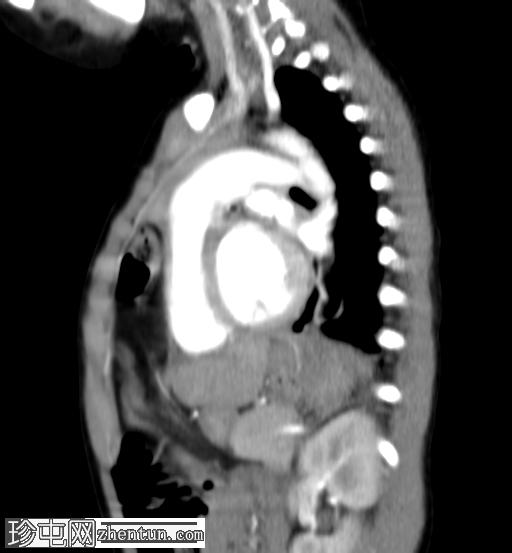

矢状位增强扫描

动脉期

横结肠及其系膜经膈前部缺损疝入前纵隔。

未见肠管扩张或梗阻。